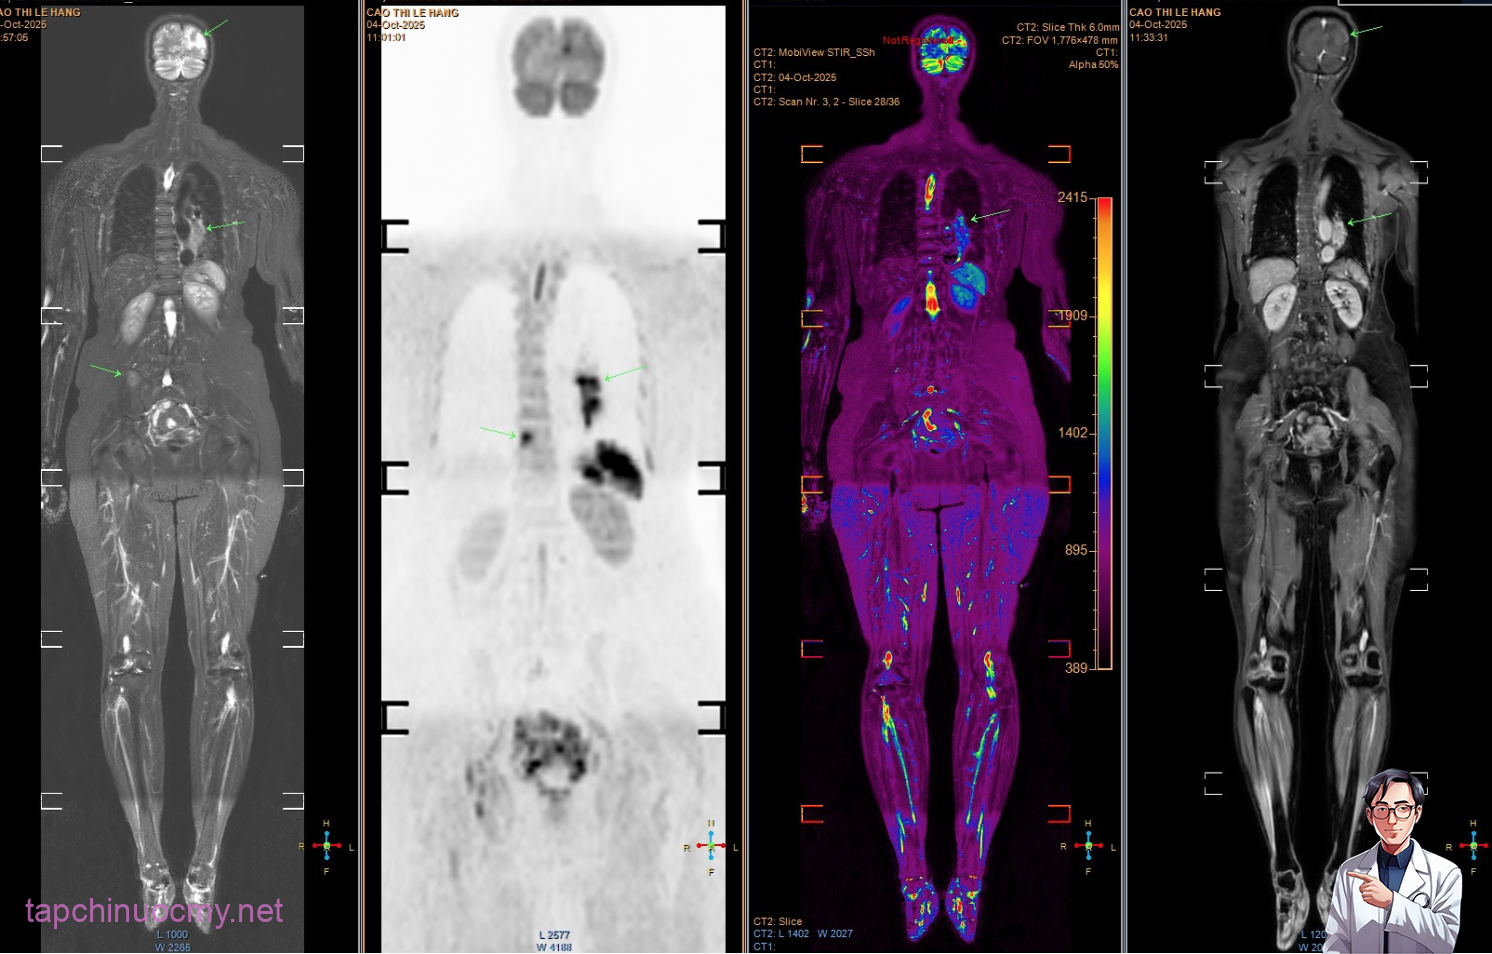

Tuy nhiên, các triệu chứng ngày càng nhiều và nặng hơn, bệnh nhân mới chịu đi khám sức khỏe. Kết quả chụp MRI cho thấy nhiều ổ tổn thương di căn dạng biểu mô tuyến. Khi chụp CT ngực, bác sĩ phát hiện một khối u lớn ở đáy phổi trái, xác định là ungthư phổi giai đoạn muộn, đã di căn sang nhiều cơ quan, trong đó có não bộ. Tiên lượng bệnh rất xấu.

Hình ảnh chụp tổn thương di căn của bệnh nhân. (Ảnh: Bác sĩ cung cấp)